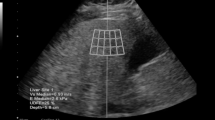

The patient was in the supine position with the right upper extremity extended above the head to stretch the intercostal muscles and obtain the proper scanning window during the examination. First, B-mode US images were scanned to detect if any focal liver lesion existed. Second, the UGAP mode was activated, and examinations were performed on liver segment V, inferior to the right anterior lobe, through the intercostal space, with the transducer perpendicular to the skin surface while the participant held his or her breath for 3–5 s. Third, since the depth of region of interest (ROI) is fixed from 4 to 8 cm, the operator can only move the ROI on the right and left axis to avoid bile ducts, vessels and shading artifacts (Fig. 2B). Twelve consecutive measurements on the different frames were recorded, and median and interquartile range (IQR)/median values were displayed. We defined IQR/median < 15% of twelve measurements as effective and successful measurements. The AC was calculated using the method from a prior report by Yao et al.16 and GE whitepaper.

B-mode ultrasound (US) and ultrasound-guided attenuation parameter (UGAP) measurement in a 32-year-old man with hepatic steatosis. A. B-mode US imaging shows increased hepatic echogenicity with impaired visualization of periportal echogenicity and visible diaphragm echogenicity. Both reviewers 1 and 2 assessed the degree of steatosis as moderate. B. UGAP measurement was performed in the right lobe of the liver through an intercostal scan. The level of attenuation was color-coded and displayed in the region of interest (ROI), excluding the vascular structures. The ultrasound system automatically displays the attenuation coefficient (dB/cm/MHz).